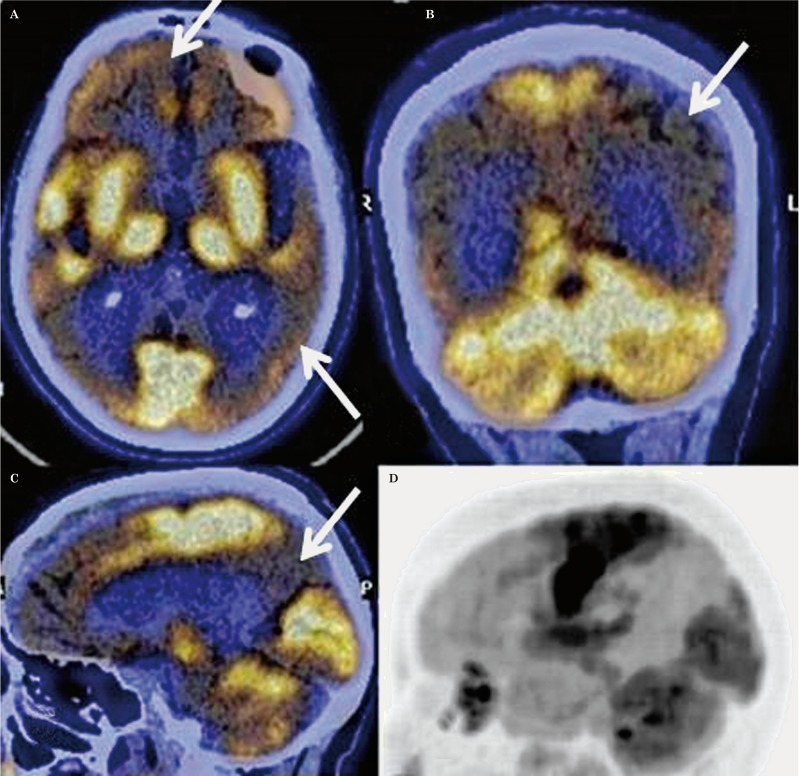

Pattern FTD: ipometabolismo predominante nei lobi frontali, nelle porzioni anteriori dei lobi temporali e nella corteccia cingolata anteriore.

(B) PCA: ipometabolismo nelle aree occipitali e parietali e un relativo ipermetabolismo nel lobo frontale.

(C) Variante logopenica dell’afasia primaria progressiva (lvPPA): mostra ipometabolismo nelle aree temporali e parietali sinistre.

(D) AD disesecutiva (dAD): ipometabolismo nella corteccia associativa eteromodale e ipermetabolismo nelle cortecce sensoriali e motorie primarie.

(E) Variante comportamentale dell’AD (bvAD): ipometabolismo nelle cortecce frontali, temporali mediali e del cingolo.

(F) bvFTD: ipometabolismo nel lobo frontale e ipermetabolismo nelle aree occipitali e parietali.